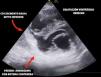

Mujer de 62 años, sin antecedentes personales, consulta por epigastralgia de cuatro días, sufriendo un ictus lacunar hemi-motor puro derecho con tomografía computarizada multimodal anodino. En el electrocardiograma se observa elevación del ST inferior con ondas Q, ingresando en la unidad de cuidados intensivos. En la ecocardiografía transtorácica se objetiva comunicación interventricular septo-basal con cara inferior aquinética, adelgazada e hiperecogénica sugestiva de pseudoaneurisma con posible ruptura miocárdica contenida (fig. 1, Video 1). Se desestima cirugía emergente ante clínica neurológica y riesgo quirúrgico por friabilidad de tejidos. A la espera de decisión final, se realiza resonancia magnética nuclear cardiaca (fig. 2), tras la que sufre parada cardiorrespiratoria en actividad eléctrica sin pulso por taponamiento con reanimación infructuosa (fig. 3, Videos 2,3). Las complicaciones mecánicas postinfarto agudo de miocardio, aunque inusuales hoy en día, siguen siendo una patología potencialmente mortal y tiempo-dependientes, donde las técnicas de imagen como la ecocardiografía siguen jugando un papel fundamental.